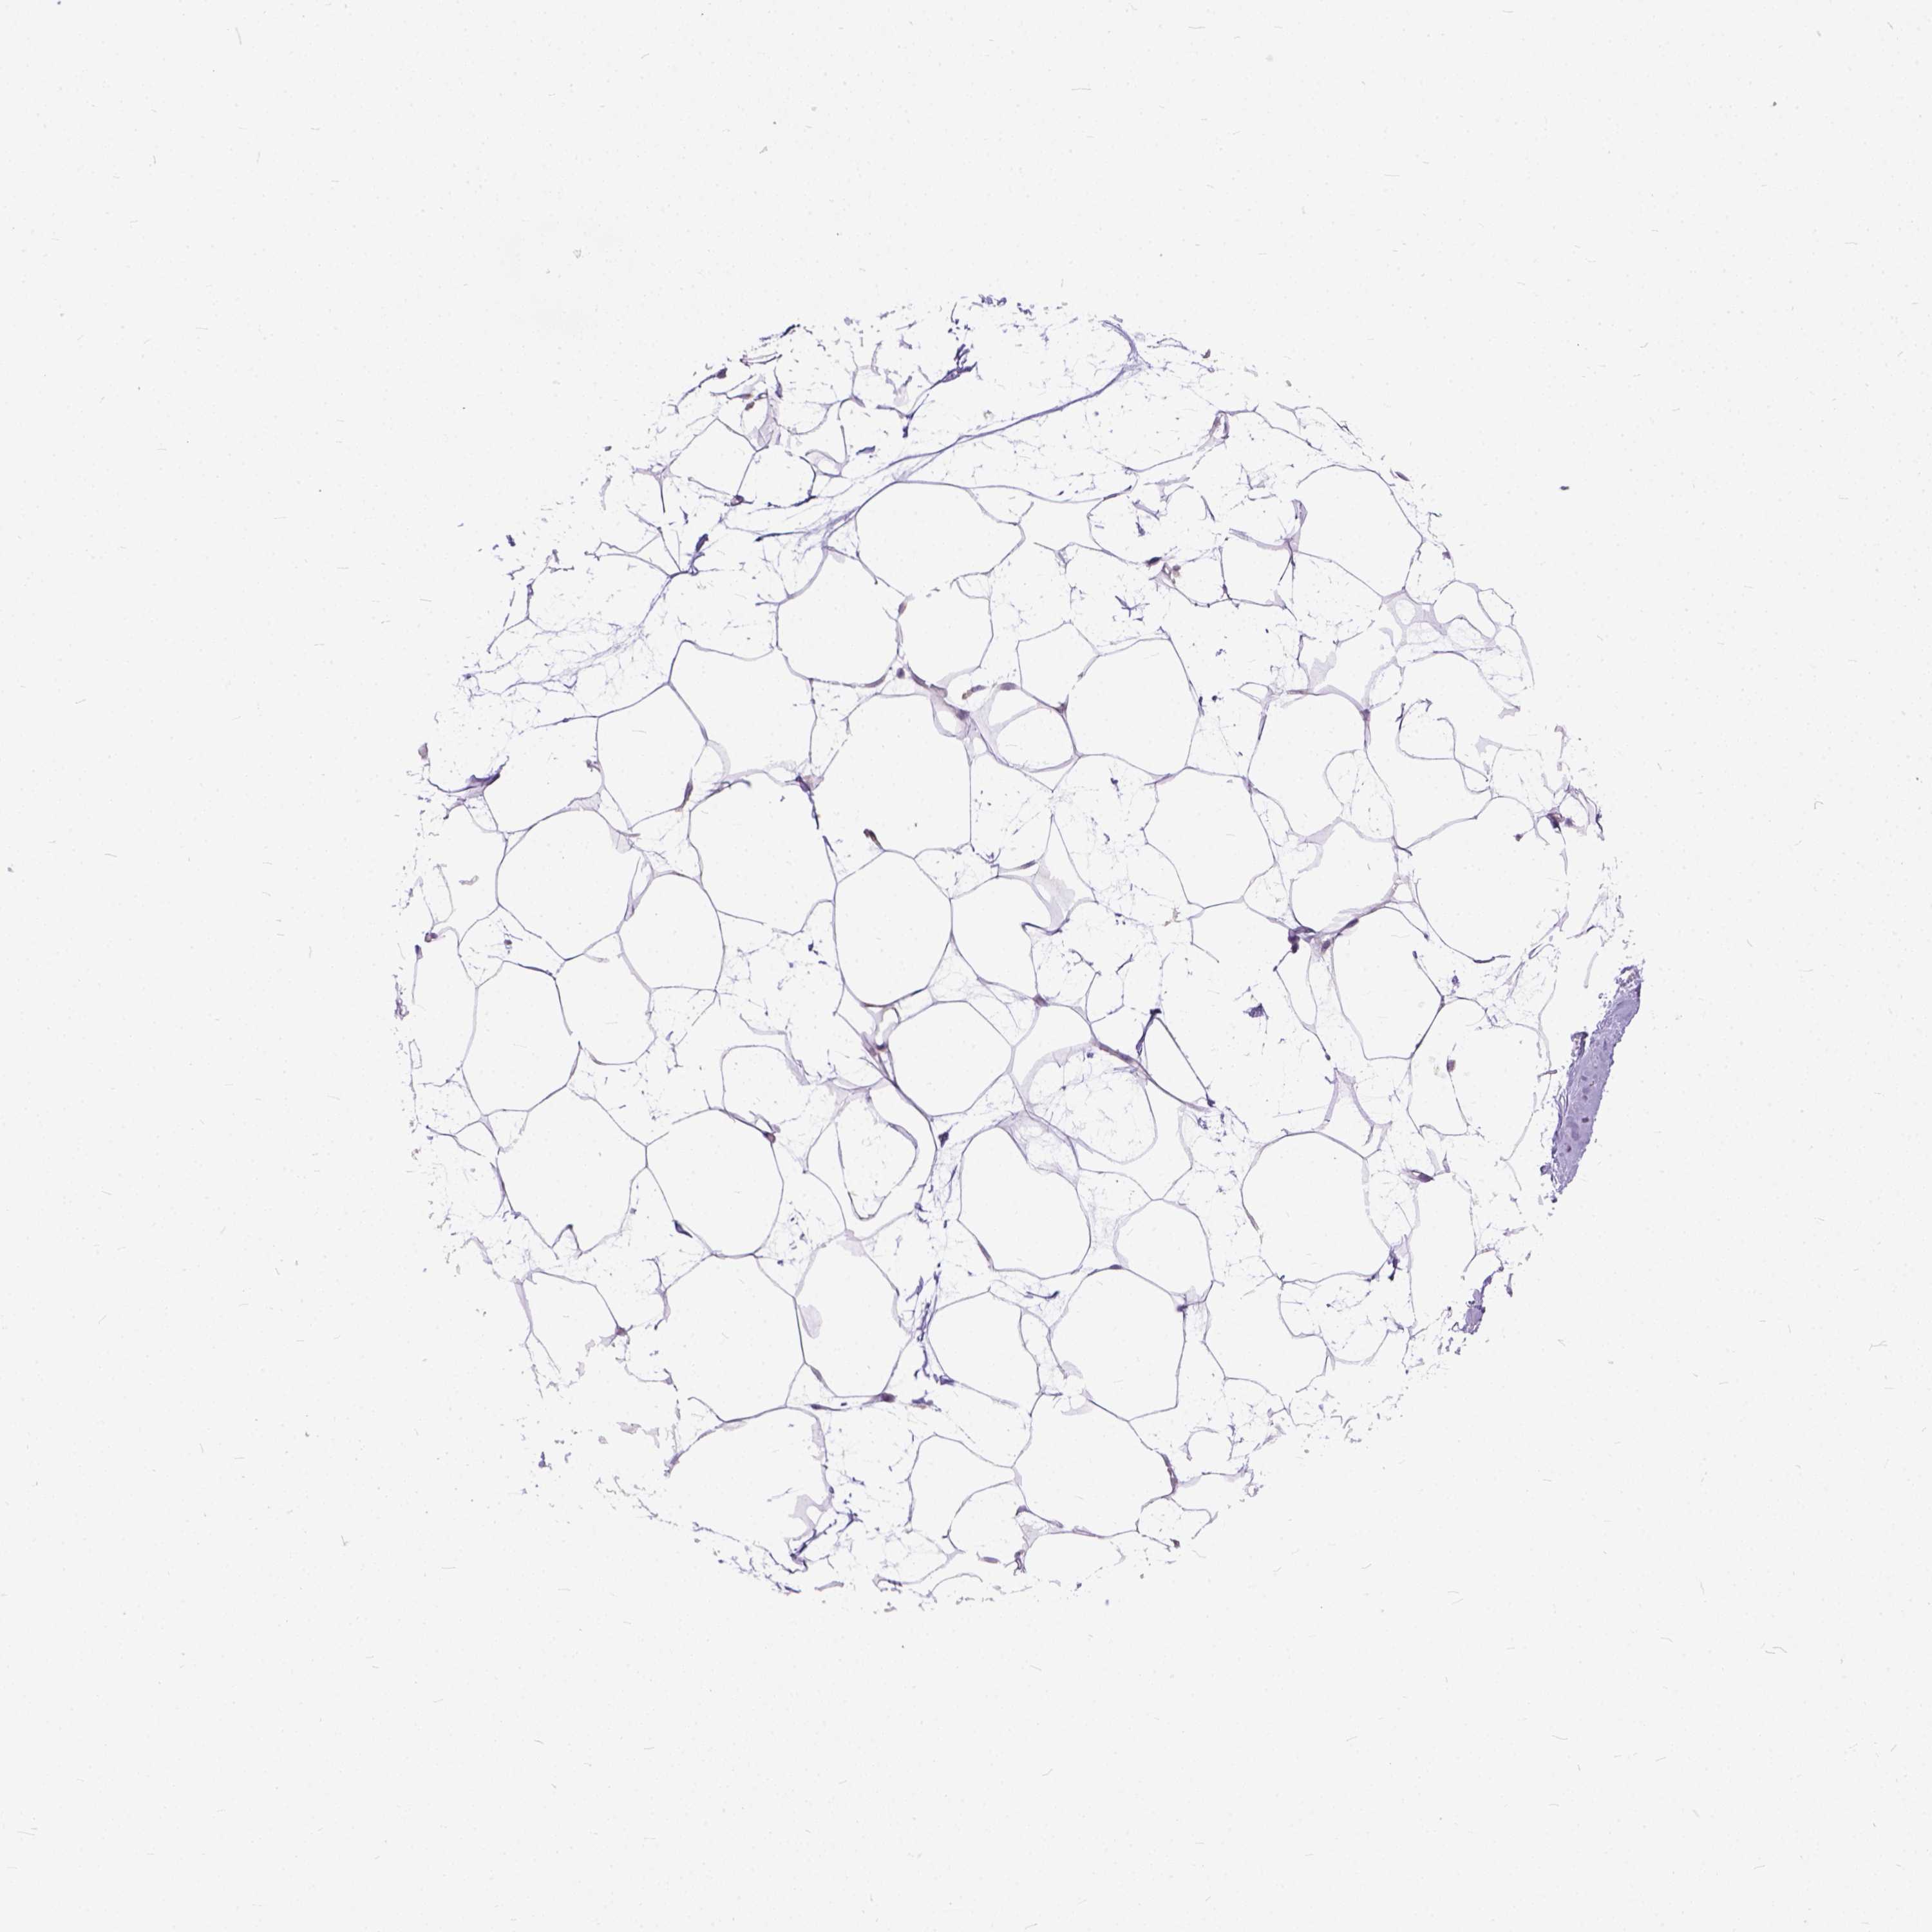

BREAST - HPA RNA-seqi

The RNA-seq details section shows detailed information about the individual samples used for the transcript profiling and results of the RNA-seq analysis.

Information about each individual sample is listed below, including gender, age, a tissue section image and estimated fractions of cell types. nTPM (normalized transcripts per million) values give a quantification of the gene abundance which is comparable between different genes and samples.

Female, age 52

Breast sample 373

nTPM: 0.3

Cell types%

Glandular cells:

15

Adipocytes:

5

Other cell types:

80